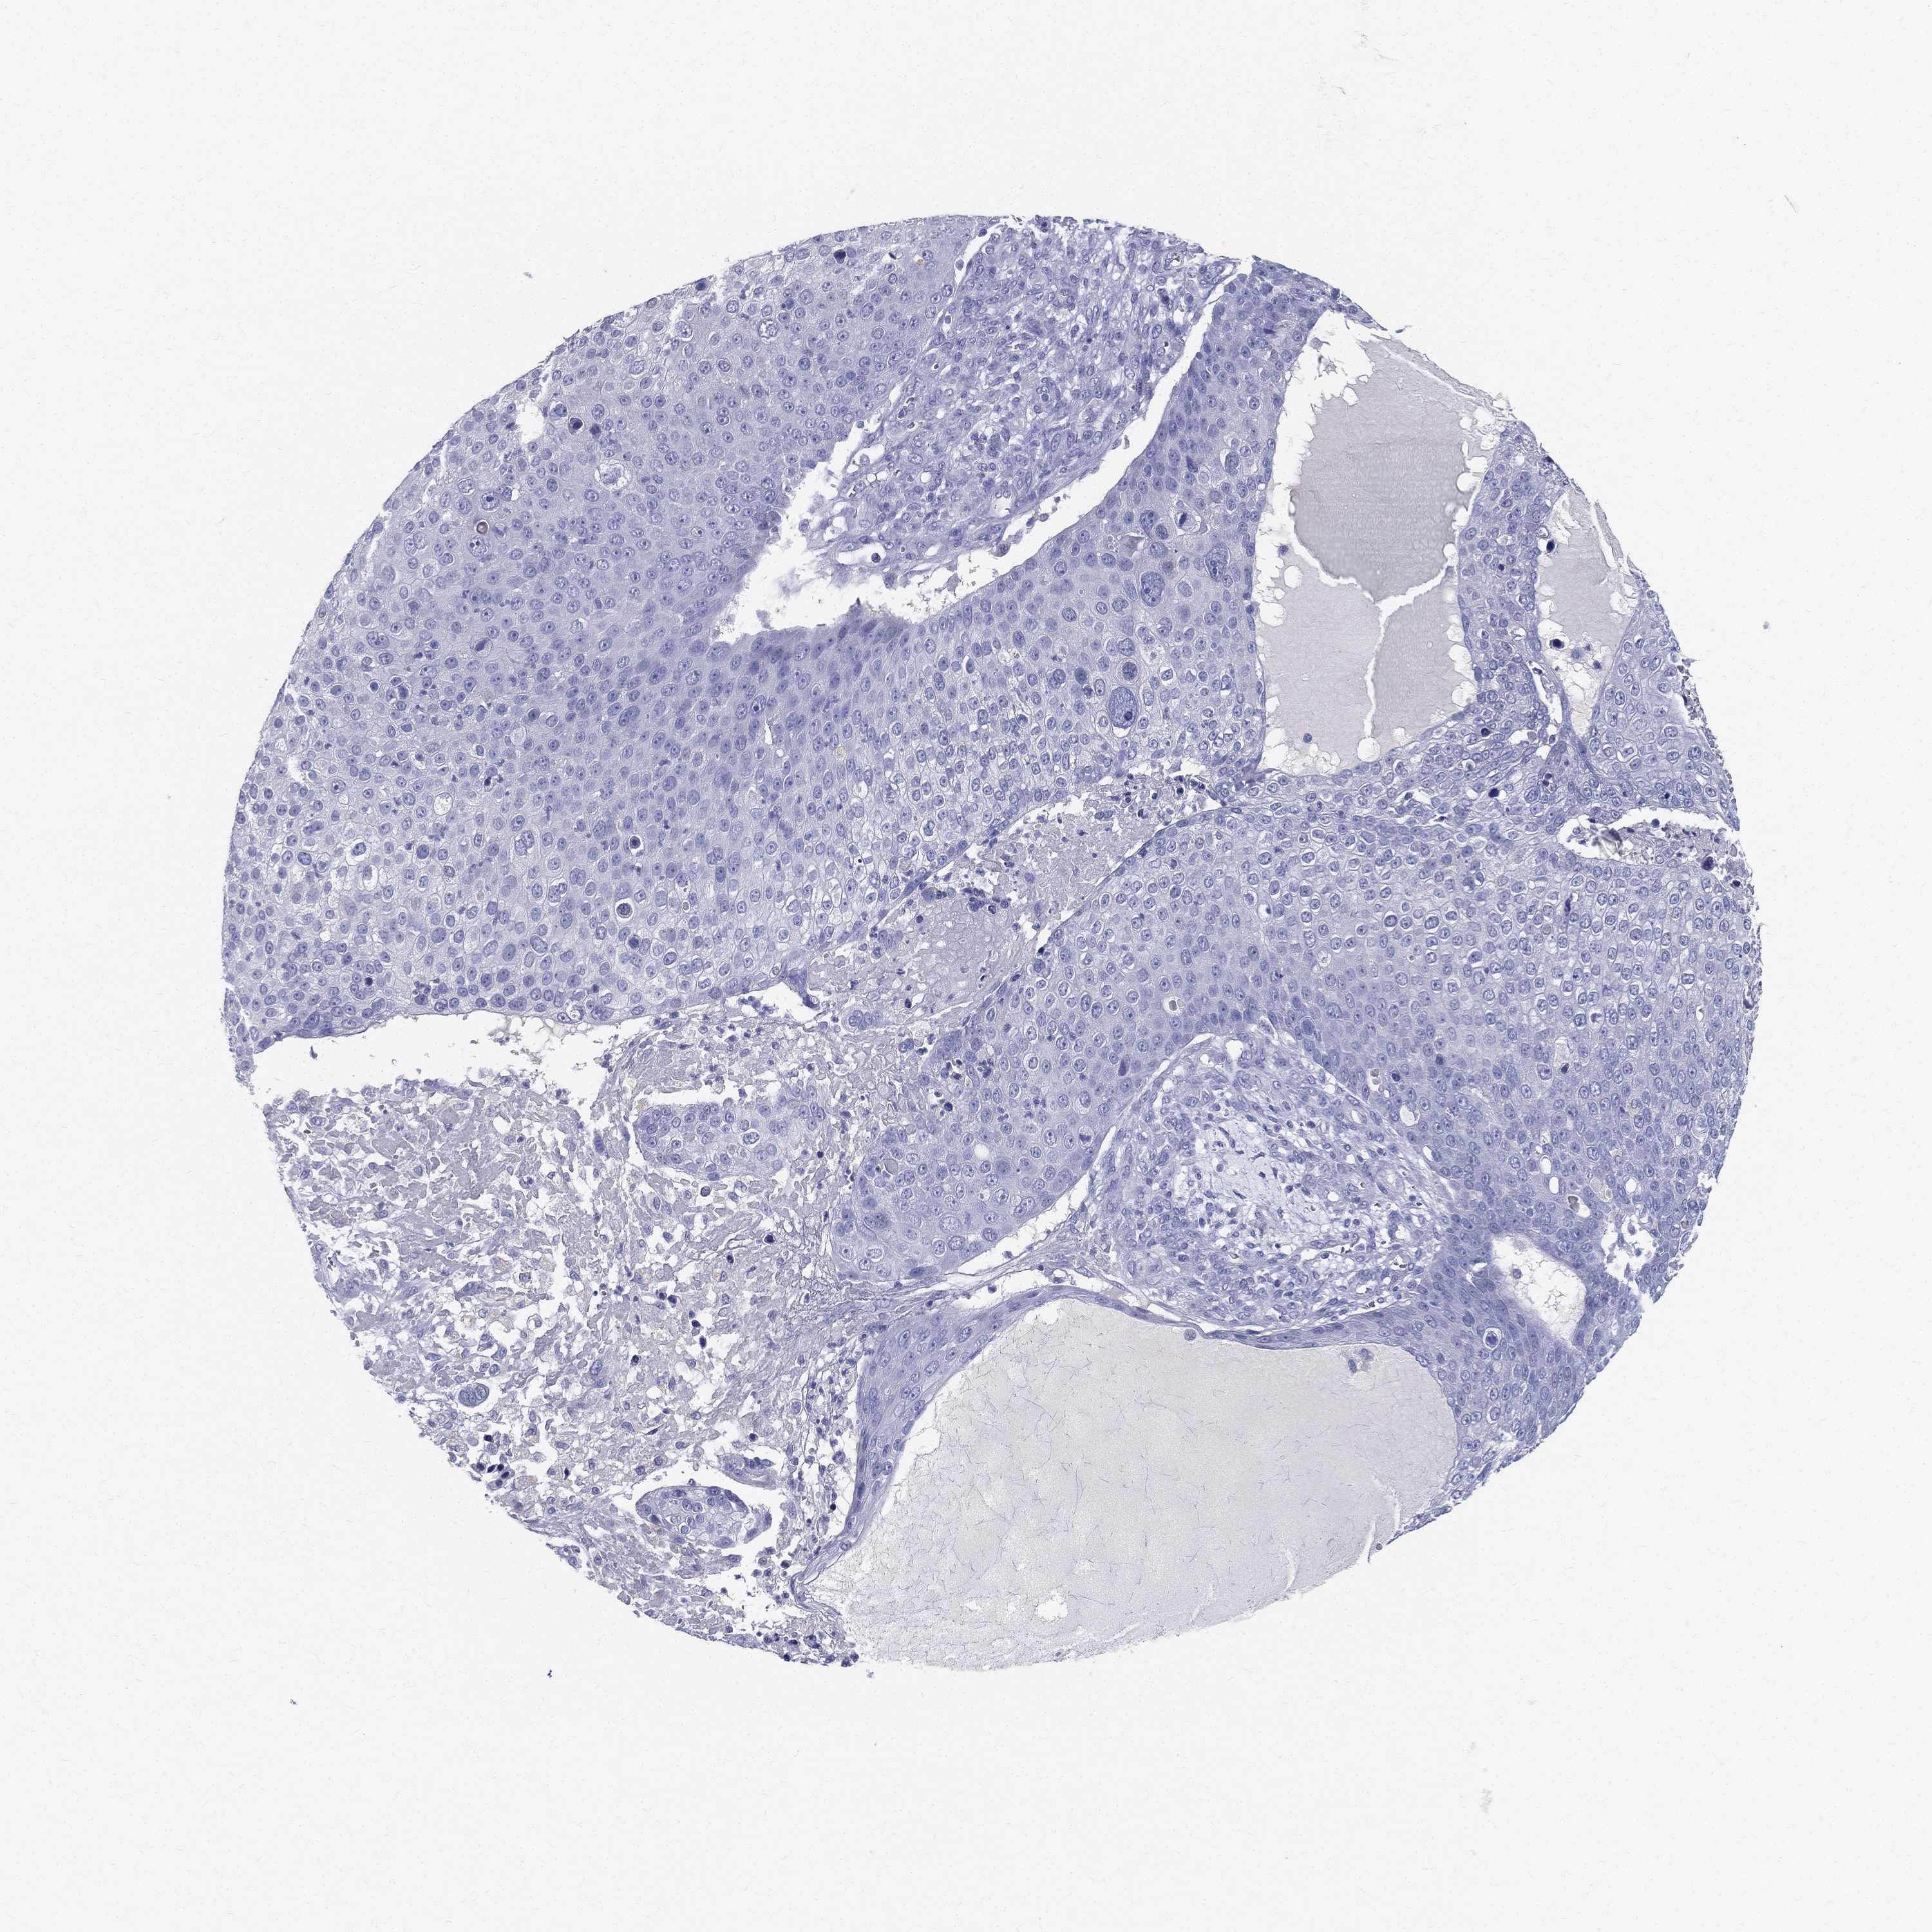

Basal cell and squamous cell cancer

SKIN CANCER - Protein expressioni

A mouse-over function shows sample information and annotation data. Click on an image to view it in a full screen mode. Samples can be filtered based on level of antibody staining by selecting one or several of the following categories: high, medium, low and not detected. The assay and annotation is described here.

Antibody stainingi

Antibody staining in the annotated cell types in the current human tissue is reported as not detected, low, medium, or high, based on conventional immunohistochemistry profiling in selected tissues. This score is based on the combination of the staining intensity and fraction of stained cells.

Each image is clickable and will lead to virtual microscopy that enables deeper exploration of all samples and also displays staining intensity scores, fraction scores and subcellular localization as well as patient and tissue information for each sample.

Antibody HPA002904

Staining

High

Medium

Low

Not detected

Intensity

Strong

Moderate

Weak

Negative

Quantity

>75%

75%-25%

<25%

None

Location

Nuclear

Cytoplasmic/membranous

Cytoplasmic/membranous,nuclear

Basal cell carcinoma

Squamous cell carcinoma, NOS